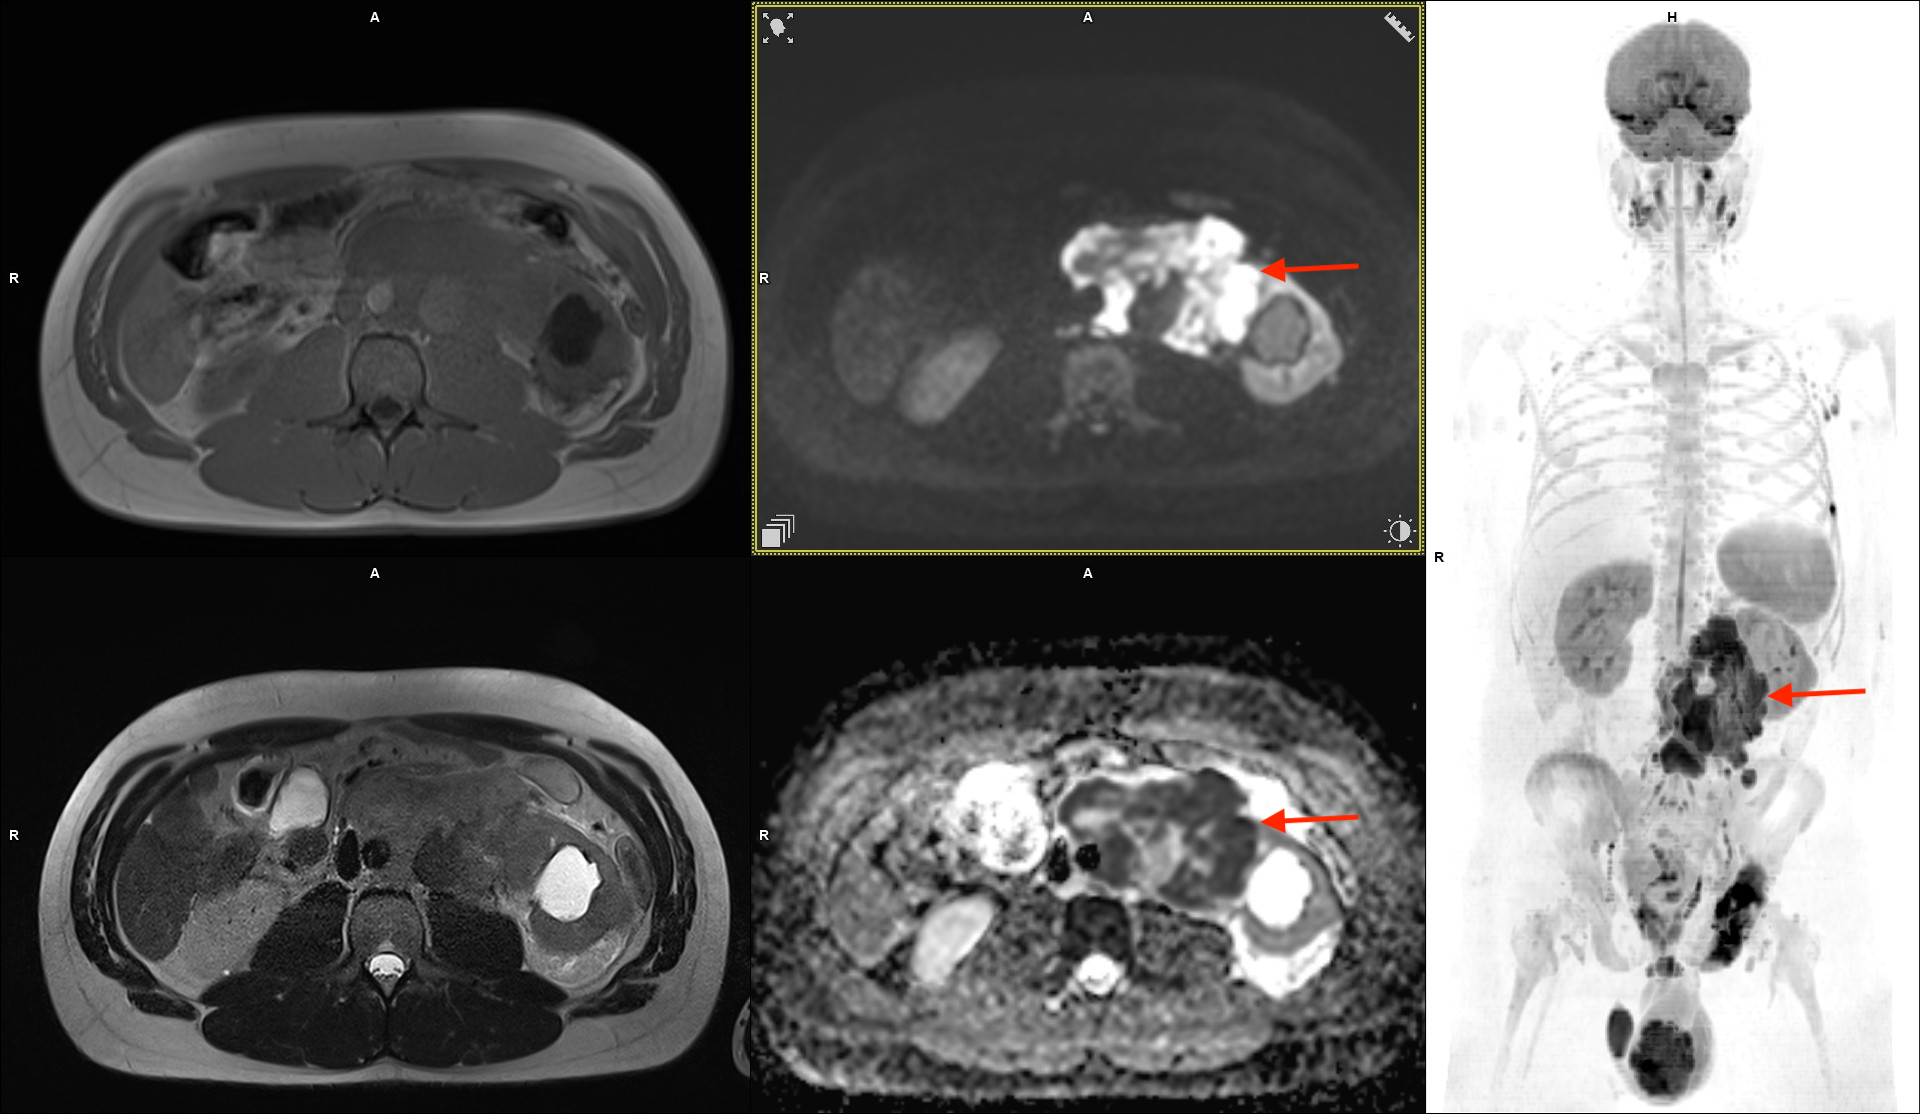

Obrazy w sekwencjach T1 w płaszczyźnie osiowej (lewy górny), T2 w płaszczyźnie osiowej (lewy dolny), DWI (środkowy górny) w płaszczyźnie osiowej, mapy ADC (środkowy dolny) w płaszczyźnie osiowej oraz obraz w sekwencjach DWI w projekcji 3D MIP. Widoczna zmiana w jądrze lewym oraz liczne zmiany mające charakter przerzutowy.